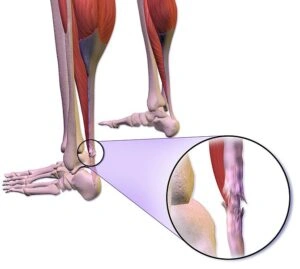

4. Retrocalcaneal Bursitis

Retrocalcaneal bursitis is characterized by pain at Achilles tendon. It is caused by chronic inflammation of bursa due to friction, supination, and overpronation. Your physician may palpate the foot to check the flexibility of calf muscles.

Chronic retrocalcaneal bursitis is followed by severe pain and swelling of the posterior soft tissue located in front of the Achilles tendon. You should also know that this type of bursitis is regularly accompanied by mid-portion insertional tendinosis.